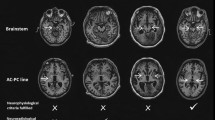

The signals used in this study were GSM-1800 MHz and UMTS-1960 MHz. At 1800 MHz, the GSM field applied was an amplitude-modulated signal with rectangular pulses at a repetition frequency of 217 Hz and a duty cycle of 1:8, yielding a frame length of 4.61 ms, each including a 576 µs burst. The UMTS signal was produced by a UMTS generator (GUS 6960S, University of Wuppertal, Wuppertal, Germany)41 coupled to an RF power amplifier (14002600-10, RFPA S.A., Artigues-près-Bordeaux, France). Head-only exposure was achieved using a loop antenna (Fig. 4).

The SAR in the brain, or BASAR, had previously been characterized at 900 MHz39 and 1800 MHz42,43. Temperature was measured inside a homogeneous gel phantom using a thermistor probe (VITEK, BSD Medical Devices, Salt Lake City, USA), 1.3 cm from the inner side of the rocket, directly below the loop. The SARs obtained from these measurements were compared with numerical simulations based on the Finite Difference Time Domain (FDTD) method. This very powerful, popular tool in bioelectromagnetics was also applied using a 7-tissue numerical rat phantom. For GSM and UMTS signals, the BASAR was 8.4 ± 0.3 and 7.9 ± 0.3 W/kg/W, at 1800 MHz and 1960 MHz, respectively.

If the BASAR is considered to be the “local” SAR level, with a 2-fold range of voxel SAR levels, then the levels in this set of experiments were 0.026 (very low), 0.26 (low), 2.6 (in the range of the ICNIRP limits for local public exposure), and 13 W/kg (in the range of ICNIRP limits for local occupational exposure).

In vivo temperatures were measured on adult, conscious, exposed rats by inserting temperature probes next to the dura matter and into the rectum. Temperature elevation in the cortex (with respect to temperature change in the rectum) was 0.9 °C at 13 W/kg (Figure S1). We noted that, immediately after the end of exposure, the relative temperature dropped very rapidly and went almost back to background levels within 5 minutes. Therefore, rats were experiencing repeatedly temperature increases in their brains during 2 hours/day, 5 days/week for 4 weeks at BASAR of 13 W/kg.

SAR values were computed for the whole head and in the regions selected for biological analysis. The SAR spatial distribution (Fig. 5a) illustrates the distribution of exposure, with the highest SAR values in the brain close to the loop antenna. The SAR values in the selected areas at 1800 MHz are shown in Fig. 5b and reported in Table 3. Similar results were observed at 1960 MHz. Comparable exposure systems and dosimetric analyses43, with assessment of the stability of the exposure system39, had been previously reported.

Dosimetric analysis of SAR in the rat brain during exposure to GSM 1800 MHz. A heterogeneous rat model was used to evaluate local SAR in the selected regions. (a) Global view of the rat phantom in the rocket with the loop antenna matched at 1800 MHz and 3D view of brain SAR distribution. (b) SAR corresponding to the selected regions.